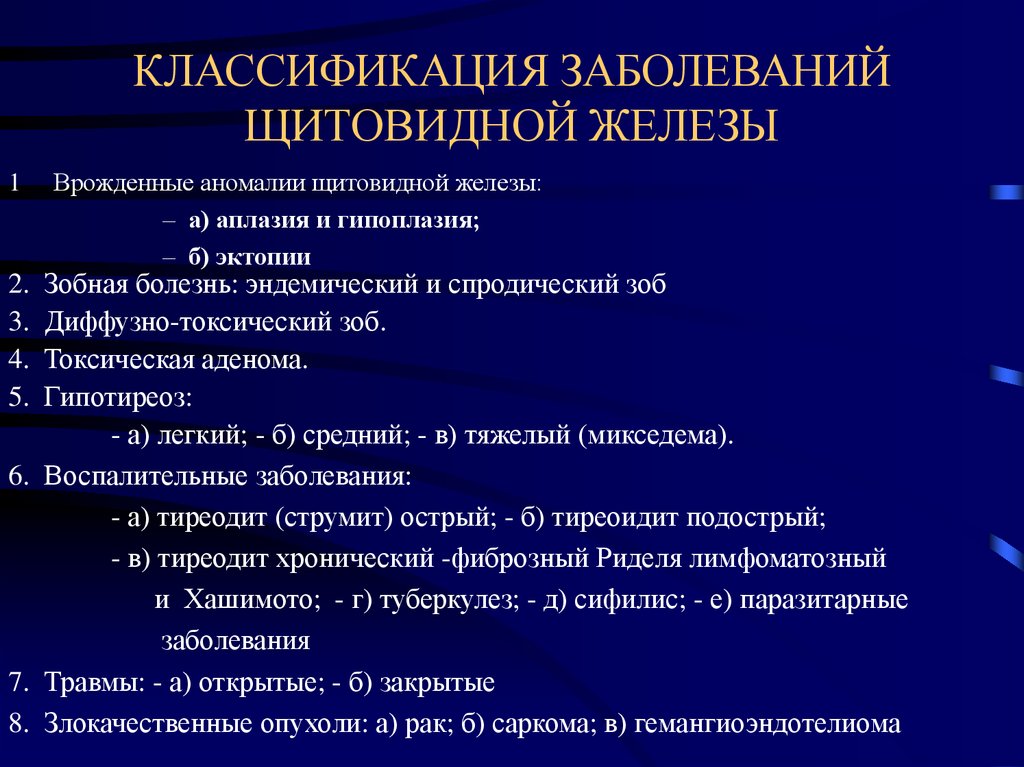

Амебиазный абсцесс печени. Солитарный абсцесс печени. Амебный абсцесс печени кт. Злокачественные опухоли щитовидной железы классификация. К злокачественным новообразованиям щитовидной железы относятся:. Доброкачественные щитовидной железы классификация. Доброкачественные новообразования щитовидной железы.

Злокачественные опухоли щитовидной железы классификация. К злокачественным новообразованиям щитовидной железы относятся:. Доброкачественные щитовидной железы классификация. Доброкачественные новообразования щитовидной железы. Классификация заболеваний щитовидной железы. Классификация хирургических заболеваний щитовидной железы. Заболевания щитовидной железы классификация этиология. 1. Классификация заболеваний щитовидной железы?.

Классификация заболеваний щитовидной железы. Классификация хирургических заболеваний щитовидной железы. Заболевания щитовидной железы классификация этиология. 1. Классификация заболеваний щитовидной железы?. Опухоль печени доброкачественная кт. Первичные злокачественные опухоли печени. Злокачественные новообразования печени кт. Первичные и Метастатические опухоли печени.